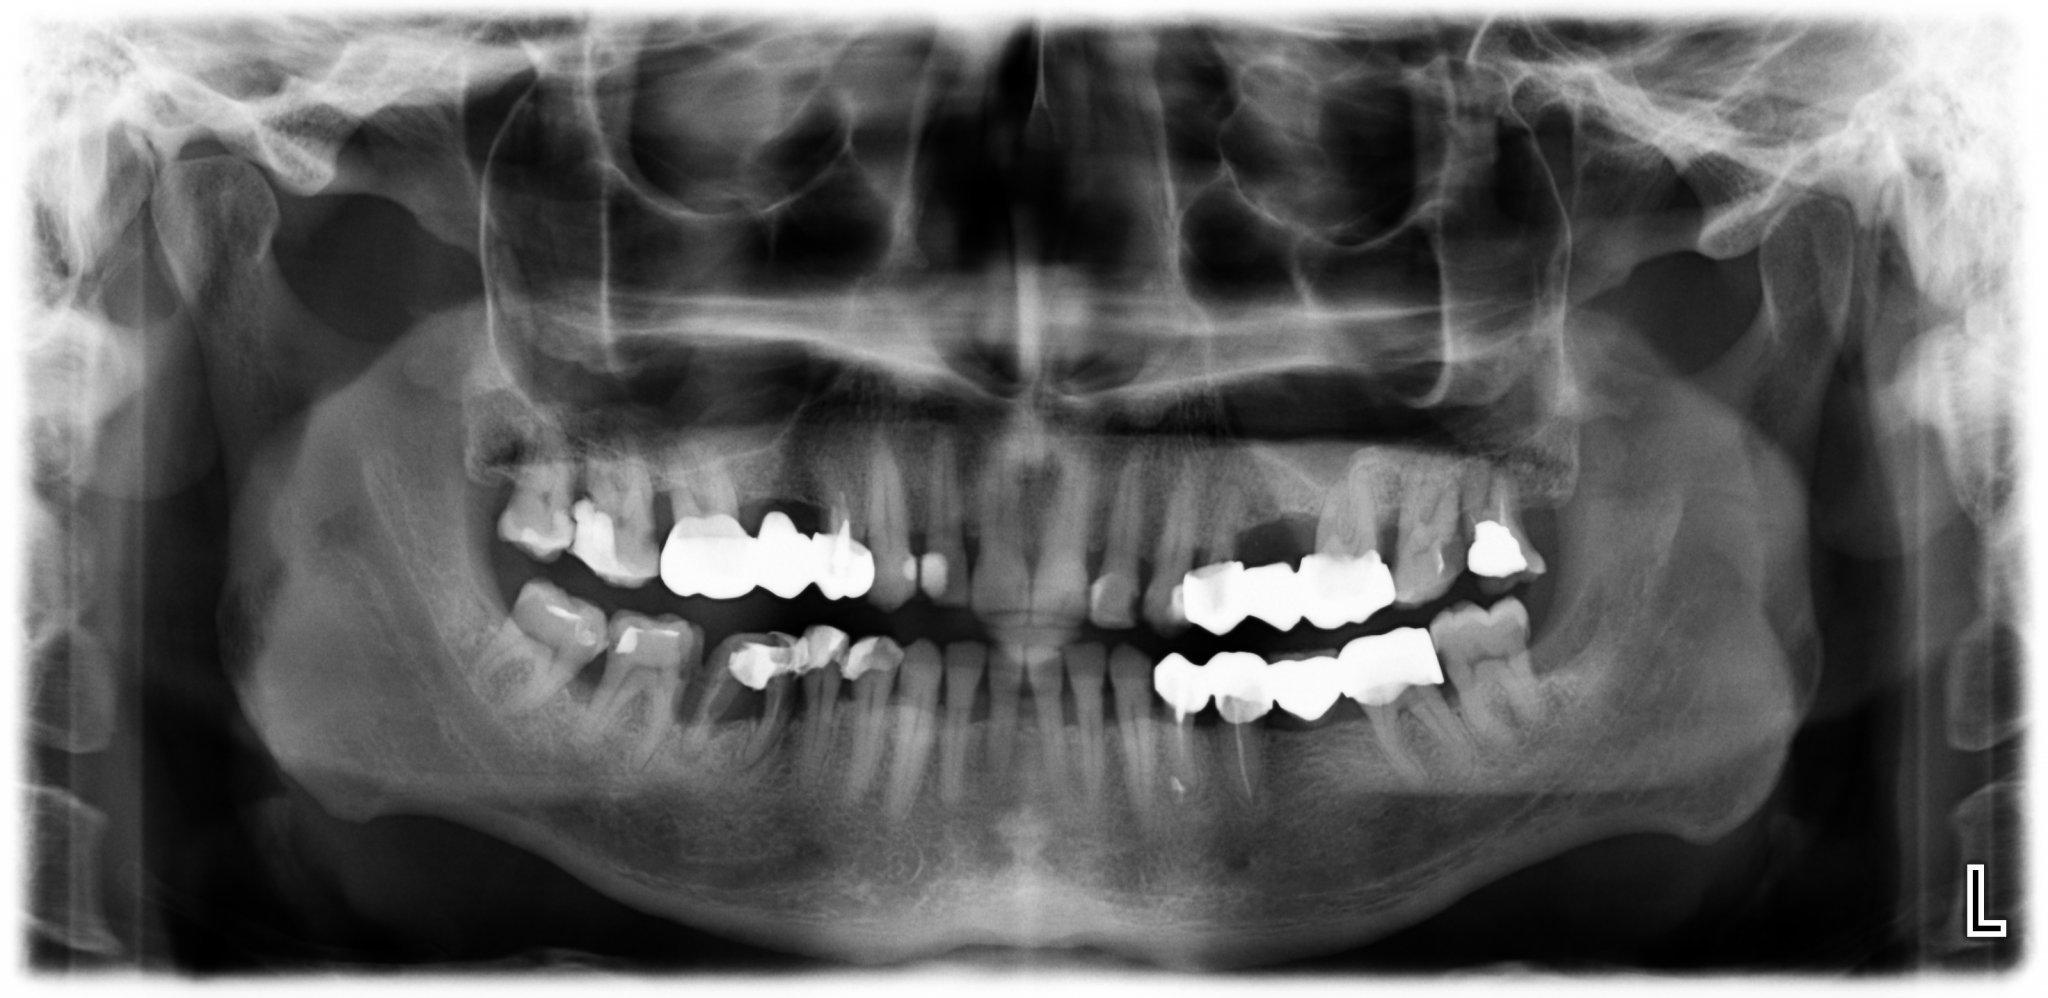

На снимката 6-ти долу вдясно е изваден. Ще се прави мост. Стоматологът ми се двоуми моста на 5-ти и 7-ми ли да стъпи или да включи и 4-ти.

Ще се радвам на компетентното ви мнение, за което Благодаря още от сега !

buty, причините да иска да включи и 4ти зъб най-вероятно са, че е с доста голяма обтурация (пломба) и стопяването на костта около 6ти зъб. Не е лош вариант. Simple Smile

Аргументите са, че от една страна пломбата на 4-тия е голяма, другото е, че моста ще е по-стабилен ако е и върху 4-тия. Странното е, че стоматолога иска аз да реша кой от двата варианта да се осъществи, а не той(тя).

Не съм стоматолог, но като пациент с пародонтит виждам че костта е стопена доста от кэм петия зъб, седмият също е с оголени корени...колко ще са стабилни тези мостоносители 5 и 7 с това стопяване ?

# 704

buty, конструкцията ще стане по-стабилна, ако се включи и 4ти зъб, предвид състоянието на другите два.